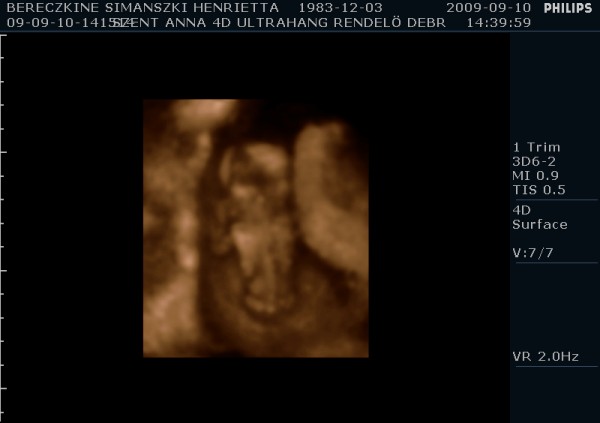

Megjöttem én is ismét, tettem fel képeket. A párom ragaszkodott hozzá, hogy kérjünk DVD-t, így hát átkapcsoltak 4D-be is. Kb. 10-15 perc lett a dvd, nagyon jópofa, látszik mindene. Mozognom, köhögnöm kellett nekem is, hogy a baba felébredjen, de amikor ébren volt, hihetetlen mit művelt. Egyik helyről a másikra átment, az első képen épp ez látható. :-) Ott a lábai vannak alul, a térdei nagyon jól látszanak. Épp ekkor rúgta át magát egy neki kényelmesebb pozícióba. :-)

A második képet meg csak azért tettem fel, hogy ez is legyen, de majd próbálok még a filmből kiszedni jobb képeket. Ezeket a párom csinálta 2 perc alatt.